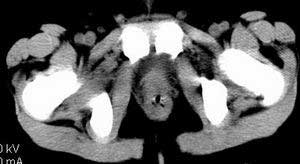

| 患者,男,9岁,因右下腹包块入院,血象不高,不规则发热,常超40度。 平扫: ![]() ![]() ![]() ![]() ![]() ![]() ![]() ![]() ![]() ![]() ![]() ![]() ![]() ![]() ![]() ![]() ![]() ![]() 增强: ![]() ![]() ![]() ![]() ![]() ![]() ![]() ![]() ![]() ![]() ![]() ![]() ![]() ![]() jiajie发言:骶椎右前区不规则软组织肿块,边缘光整,密度均匀,增强后均匀强化,右腹股沟区可见肿大淋巴结,临床有时发热,考虑淋巴瘤,儿童盆腔肿瘤应与神经母细胞瘤和横纹肌肉瘤鉴别。 longzhanghui发言:印象:盆腔右后壁不规则软组织肿块,并向前延伸.似为多个肿块融合,呈中等强化.初步考虑淋巴瘤. 听蝉观竹发言:右侧髂内、外组淋巴结肿大,从其形态和融合的情况看,同意大家意见-----考虑恶性病变,但是9岁男孩还要注意检查睾丸情况,有无隐睾? 常常类似情况是隐睾发生精原细胞瘤淋巴结转移,这个病例也要注意这一点!!! 广东凌发言:大家好,在这里我想说一下个人观点,我建议上传图片的同志能否辛苦一点就是把病史和图片都上传完整一点,比如这个病人的腹膜窗,并且这个病人的肠道的准备也是不怎么好,就从现有的质料看:病灶属于淋巴结肿大当无大的争议,有融合趋势,其内无坏死,边缘强化为主,故考虑:淋巴瘤!建议用腹膜窗看一下和肠道的关系! 阿圣发言:病灶属于淋巴结肿大当无大的争议,有融合趋势,其内无坏死,边缘强化为主,故考虑:淋巴瘤 结果是:淋巴瘤 病例来源:ct762。由宁静致远发布: http://www.radinet.com.cn/forum_view.asp?forum_id=4&view_id=2182 |